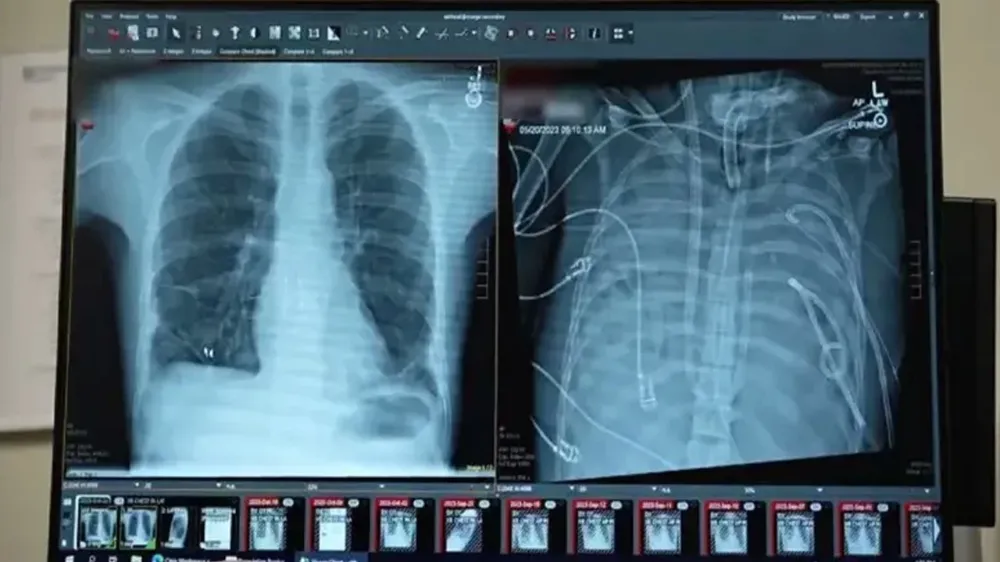

Yapay akciğer teknolojisi, organ nakli bekleyen hastalar için biyolojik donör bağımlılığını sona erdiren tıbbi bir devrime dönüştü. Geliştirilen taşınabilir sistemler, terminal safhadaki hastaların yaşam süresini ve kalitesini kalıcı olarak artırdı.

Geliştirilen yeni nesil yapay akciğer teknolojileri, organ yetmezliği çeken hastalar için biyolojik nakil zorunluluğunu ortadan kaldıran bir dönemi başlattı.

Laboratuvar ortamında optimize edilen bu cihazlar, son klinik testlerde yüksek biyouyumluluk sergileyerek terminal safhadaki hastalar için kalıcı bir çözüm haline geldi.

Dünya genelinde akciğer hastalıkları nedeniyle nakil bekleyen binlerce hasta için tıbbi teknolojide çığır açan bir gelişme yaşandı.

Geleneksel olarak sadece nakil sürecine kadar "köprü" görevi gören destek cihazları, yerini artık vücut içine tamamen entegre edilebilen ve biyolojik bir organ gibi işlev gören yapay akciğerlere bıraktı.